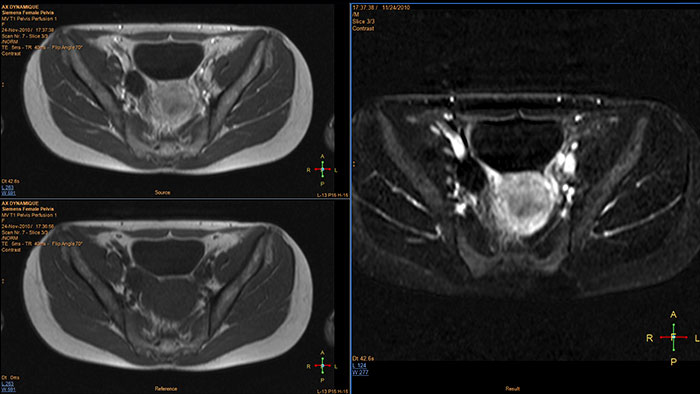

T1 Perfusion

MR T1 Perfusion

Support in assessing lesions by reviewing blood supply characteristics

Designed to evaluate time intensity curves of a T1 signal enhancement series. The application produces measurements including relative enhancement, maximum enhancement, time to peak (TTP), and wash-in/wash-out rates.

Benefits

• The package includes user-selected color-coding of the parametric maps which can be viewed and stored as overlays on anatomical reference images.

• The opacity of the overlay is user-defined.

• The series can be referenced to any other series such as Diffusion data within the same study.